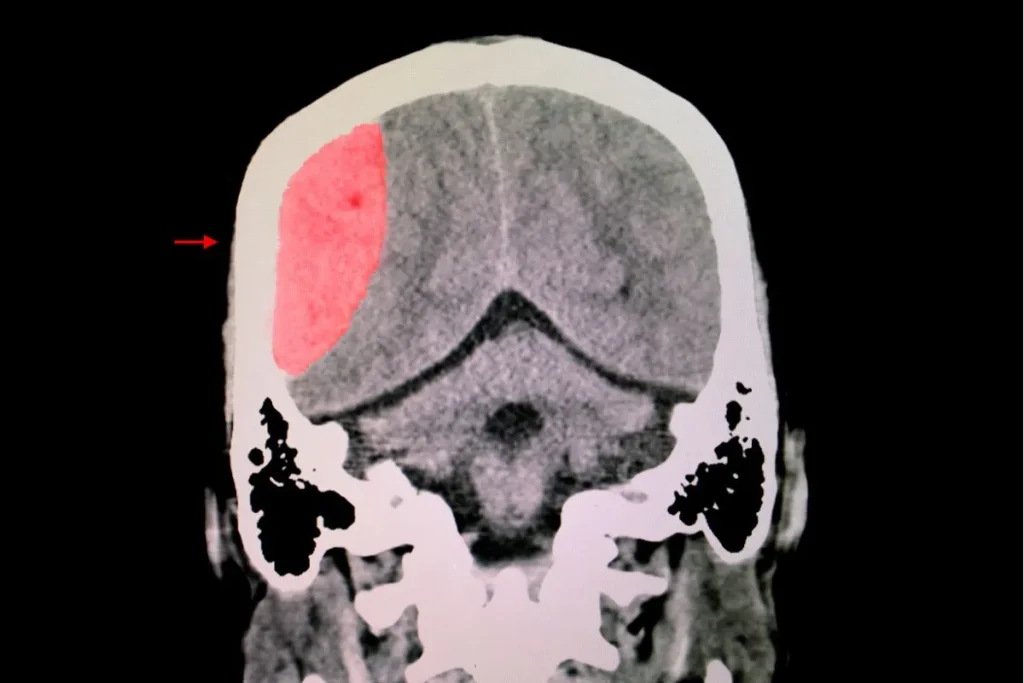

Traumatic Brain Injury (TBI) is a condition often associated with sports injuries, falls, accidents, and other traumatic events, with millions of people affected worldwide. The Centers for Disease Control and Prevention (CDC) reported 2.87 million TBI-related emergency room visits in 2014, and a staggering 817,000 children received treatment for TBI-related head injuries. The Vulnerable Brain […]

Background: Recent clinical studies in stroke and traumatic brain injury (TBI) victims suffering chronic neurological injury present evidence that hyperbaric oxygen therapy (HBOT) can induce neuroplasticity. Objective: To assess the neurotherapeutic effect of HBOT on prolonged post-concussion syndrome (PPCS) due to TBI, using brain microstructure imaging. Methods: Fifteen patients afflicted with PPCS were treated with […]